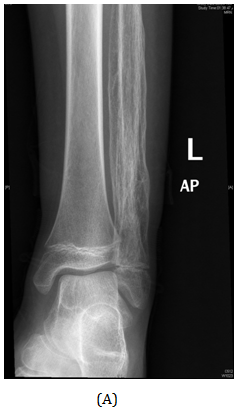

Figure 12 AP view of plain X-ray of the right leg showed ill-defined lesion involved distal end of the fibula (diaphysis) with cortical destruction and soft tissues swelling.

A Saudi girl, 10 years old presented to OPD with progressive swelling of the right ankle for 3 months, localized on the lateral aspect, and increasing with pain and swelling within last two months. During physical examination, proximal area of the skin over the swelling was dark black as what was noted. The patient was investigated primarily in a hospital outside of Riyadh according to a biopsy was taken with osteomyelitis of distal fibula and treatment was start taken but with no response. X-ray of the right leg (Figure 12) and CT of the lower limb (Figure 13). An expansile, lytic and destructive bone lesion is seen involving the distal third of the right fibula. (Figure 14) on MRI showed there is a large destructive bone lesion involving the distal third of the right fibula with sparing of the distal fibular epiphysis. No definite involvement of the right tibia and talus. Trace of fluid is seen in the right tibiotalar joint most likely reactive. The neurovascular structures appear intact. This was followed by technetium-99m MDP scintigraphy (Figure 15), what it showed a solitary focal lesion distal end of right fibula compatible with suspected Ewing's sarcoma. No additional lesions were noted to suggest skip lesions or metastasis. She treated as per Ewing sarcoma protocol in our hospital. Patient was put on neoadjuvant chemotherapy. Later, We did a wide surgical resection of the tumor was preformed upto12 cm from the distal fibula malleolus during which ,the superficial peroneal nerve and peroneus longus and brevis tendon were sacrificed the ruminant of the peroneus longus and calcaneo fibular ligament were sutured and using anchors were attached to the distal tibia in the right leg free pedicle latissmuss dorsi flap was anastomosed to the peroneal artery locally to cover the soft tissue defect by the plastic surgery team. The last MRI done for the patient (Figure 16) showed there is interval reduction in the size of the previously noted heterogeneous enhancing mass at the distal metaphysis of the right fibula. On the bone scan (Figure 17), there is interval reduction in the size of the previously noted heterogeneous enhancing mass at the distal metaphysis of the right fibula. There is no sign of skip metastases to other limb. Bilaterally bone marrow signal changes are most likely related to chemotherapy. The patient will follow up with us regularly.